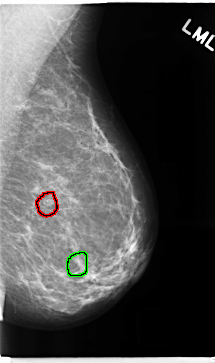

C_0271_1.LEFT_MLO

LEFT_MLO LINES 4712 PIXELS_PER_LINE 2784 BITS_PER_PIXEL 12 RESOLUTION 50 OVERLAY

FILE: C_0271_1.LEFT_MLO.OVERLAY

TOTAL_ABNORMALITIES 2

ABNORMALITY 1

LESION_TYPE CALCIFICATION TYPE PUNCTATE DISTRIBUTION CLUSTERED

ASSESSMENT 3

SUBTLETY 4

PATHOLOGY BENIGN

TOTAL_OUTLINES 1

BOUNDARY

ABNORMALITY 2

ASSESSMENT 4

SUBTLETY 5